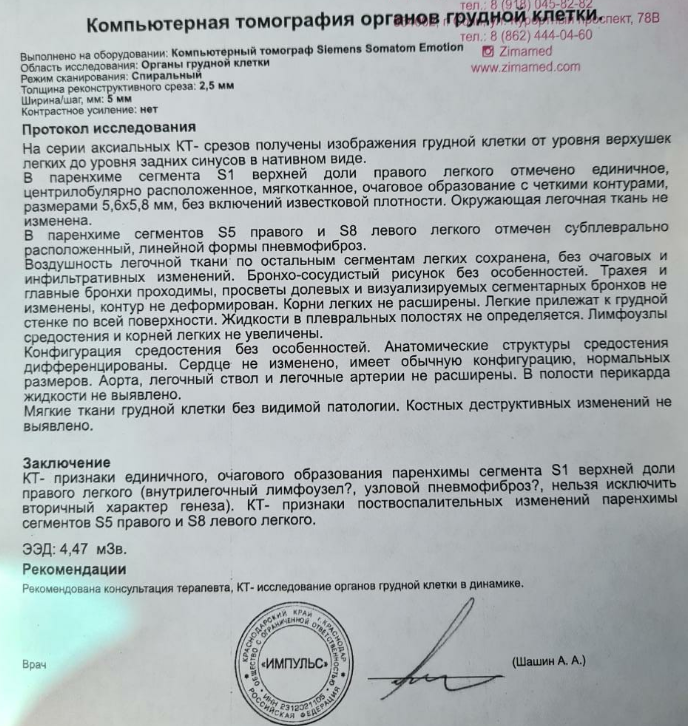

Фотографии и снимки КТ легких без контрастных веществ

Раздел: Визуальный дайджест